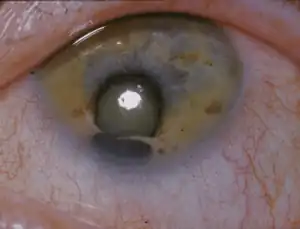

| An example of the defect after which CES is named | |

- Unilateral or bilateral iris coloboma (absence of tissue from the colored part of the eyes)

The term "cat eye" syndrome was coined because of the particular appearance of the vertical colobomas in the eyes of some patients, but over half of the CES patients in the literature do not present with this trait.[6]